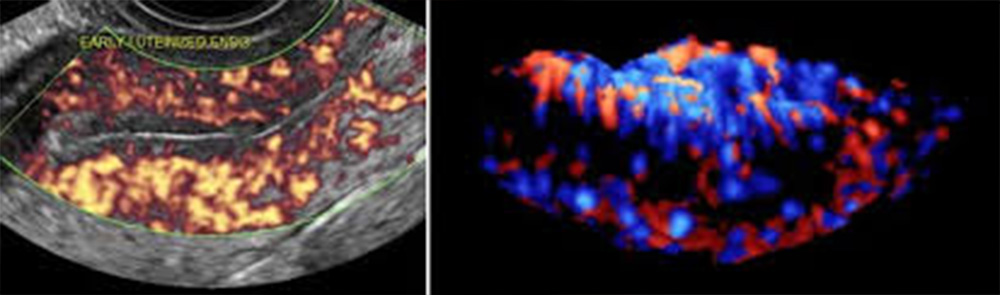

Η έγχρωμη τρισδιάστατη υπερηχογραφία (3-DPD), είναι μία αναβάθμιση του έγχρωμου Doppler, απεικονίζοντας το αγγειακό σύστημα στις τρεις διαστάσεις, με φόντο μια γκρίζα κλίμακα, που απεικονίζει μαλακούς ιστούς, δίνοντας έτσι εικόνα παρόμοια με αυτή της αγγειογραφίας, αφού επιτρέπει την άμεση απεικόνιση των πολλαπλώς αναδιπλούμενων αγγείων και τη σχέση τους με παρακείμενους ιστούς και όργανα. Με τη χρήση της τεχνικής αυτής, επιτελείται μελέτη της αρχιτεκτονικής της μικροκυκλοφορίας του όγκου και διαχωρίζονται οι όγκοι σε καλοήθεις και κακοήθεις, αφού θεωρείται ότι η ύπαρξη ακανόνιστης αγγειακής διάταξης με πολύπλοκη ή μη γεωμετρική διακλάδωση με διασκορπισμένα αγγεία συνηγορεί υπέρ κακοήθους εξεργασίας.

Η διήθηση ελέγχεται με την απεικόνιση χαρακτηριστικών ευρημάτων της αγγειογενετικής λειτουργίας, όπως νεόπλαστα αγγεία, μικροανευρύσματα και ανώμαλες διχοτομίσεις των αγγειακών κλάδων. Η διακλάδωση των αγγείων του όγκου βασίζεται στο μαθηματικό νόμο της γεωμετρικής διακλάδωσης ενός δένδρου, όπου οι μεγάλοι κλάδοι καταλήγουν σε κλάδους μικρότερου εύρους και διαμέτρου. Αν όμως συμβεί «αλλαγή» στον κυρίως αγγειακό κλάδο, τότε «αλλάζει» και η διακλάδωση, απεικονιστικό εύρημα πρώιμης κακοήθειας.

Η τεχνική (3-DPD) αποτελεί μια απαιτητική διαδικασία από μαθηματικής και τεχνολογικής απόψεως, που βασίζεται στην αλληλεπίδραση από την ανακατασκευή της γεωμετρίας των αγγείων, χρησιμοποιώντας ευκρινείς εικόνες που λαμβάνονται από μικρές περιοχές του όγκου, με αποτέλεσμα τη μέγιστη διαγνωστική ακρίβεια.

Επομένως, η χρήση του (3-DPD) επιτρέπει την εκτίμηση φυσιολογικών, παθοφυσιολογικών και αιμοδυναμικών μεταβολών στο σώμα της μήτρας, τις ωοθήκες και στους μαστούς μέσω της εκτίμησης του φαινομένου της αγγειογένεσης.